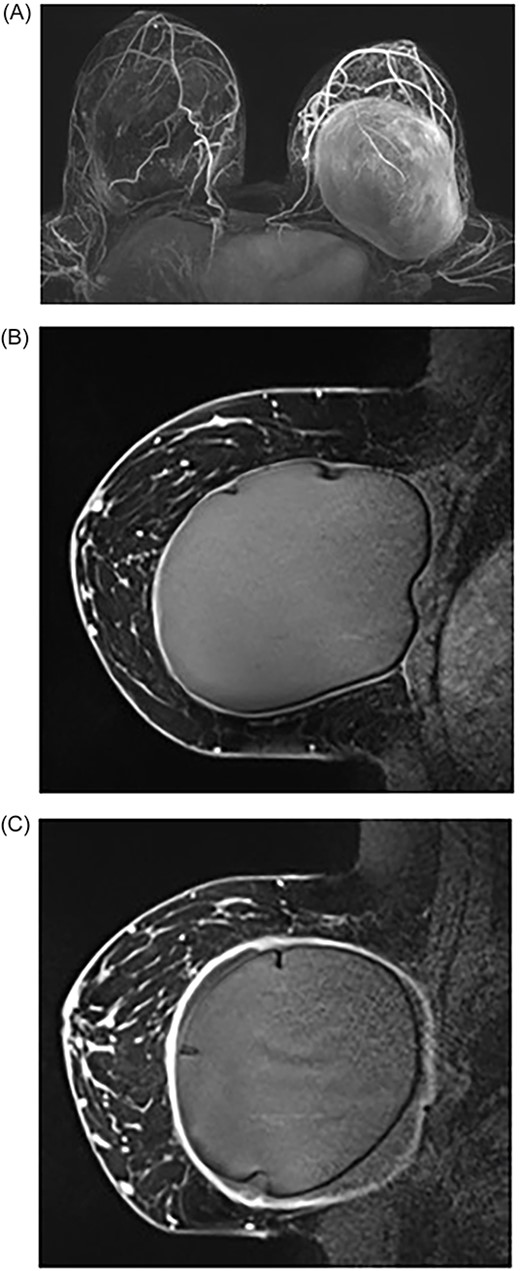

She underwent breast MRI, which showed left breast intracapsular rupture, moderate volume peri-implant fluid and diffuse thickening with avid enhancement of the fibrous capsule (Fig. 1). An US-guided left peri-implant fluid aspiration returned CD30 negative with no pathological features of breast implant-associated anaplastic large cell lymphoma (BIA-ALCL). She underwent the removal of bilateral breast implants with en bloc capsulectomy. Intraoperative findings included bilateral double capsules and outer capsules densely adhered to the ribs, muscles and breast. The inner capsules were severely contracted and significantly adherent to the underlying textured implants with bilateral thick peri implant intracapsular fluid. Both implants were removed with double capsules with subsequently no silicone or fluid spillage.

MRI of breasts showing left capsular lesion. (A) T1-weighted delayed subtraction axial MRI of breasts demonstrating intracapsular rupture with scattered foci of signal abnormalities consistent with disruptions in the silicone-matrix. (B) T1-weighted contrast sagittal MRI of right breast demonstrating mild diffuse thickening of the fibrous capsule with no nodularity and no abnormal enhancement. (C) T1-weighted contrast sagittal MRI of left breast demonstrating intracapsular rupture. The implant shell demonstrates several folds and indurations with no gross disruption